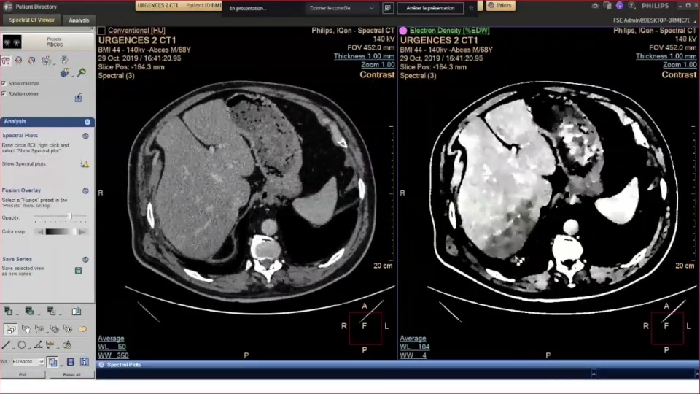

L'imagerie spectrale pour optimiser la prise en charge aux urgences

Une confiance diagnostique accrue

Une confiance diagnostique accrue et une meilleure détection

IQon Spectral CT, le scanner 100% spectral, bouleverse l’imagerie standard en proposant systématiquement deux imageries, conventionnelle et spectrale pour tout examen quel que soit le type de patient (de la pédiatrie à la bariatrie). Rapide et simple d’utilisation, cette imagerie est utilisée en routine par nos clients et s’interprète comme pour l’IRM par comparaison de différentes cartographies.

L’interprétation des données spectrales de façon rétrospective permet la mise en évidence d’un plus large champ de pathologies et une diminution significative de produit de contraste injecté en routine pour tous les patients. IQon Spectral CT est une modalité qui adresse toutes les spécialités ce qui améliore la pertinence clinique et raccourci significativement le parcours patient2.

L’interprétation systématique pour tous les patients des données spectrales MonoE bas 40Kev (pic d’énergie de l’iode) permet un rehaussement des lésions vasculaires à très faible concentration d’iode. En moyenne nos utilisateurs constatent une diminution significative des quantités de produit de contraste injecté de l’ordre de 30%. *.